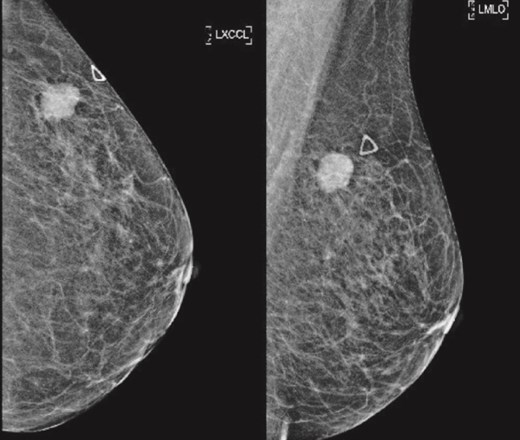

(Left) Mammography medioloateral oblique views of bilateral breasts; (Right) Mammography cranial-caudal views of bilateral breasts: Left upper central breast shows a vague focal asymmetry corresponding to the palpable concern, and several prominent right axillary lymph nodes.